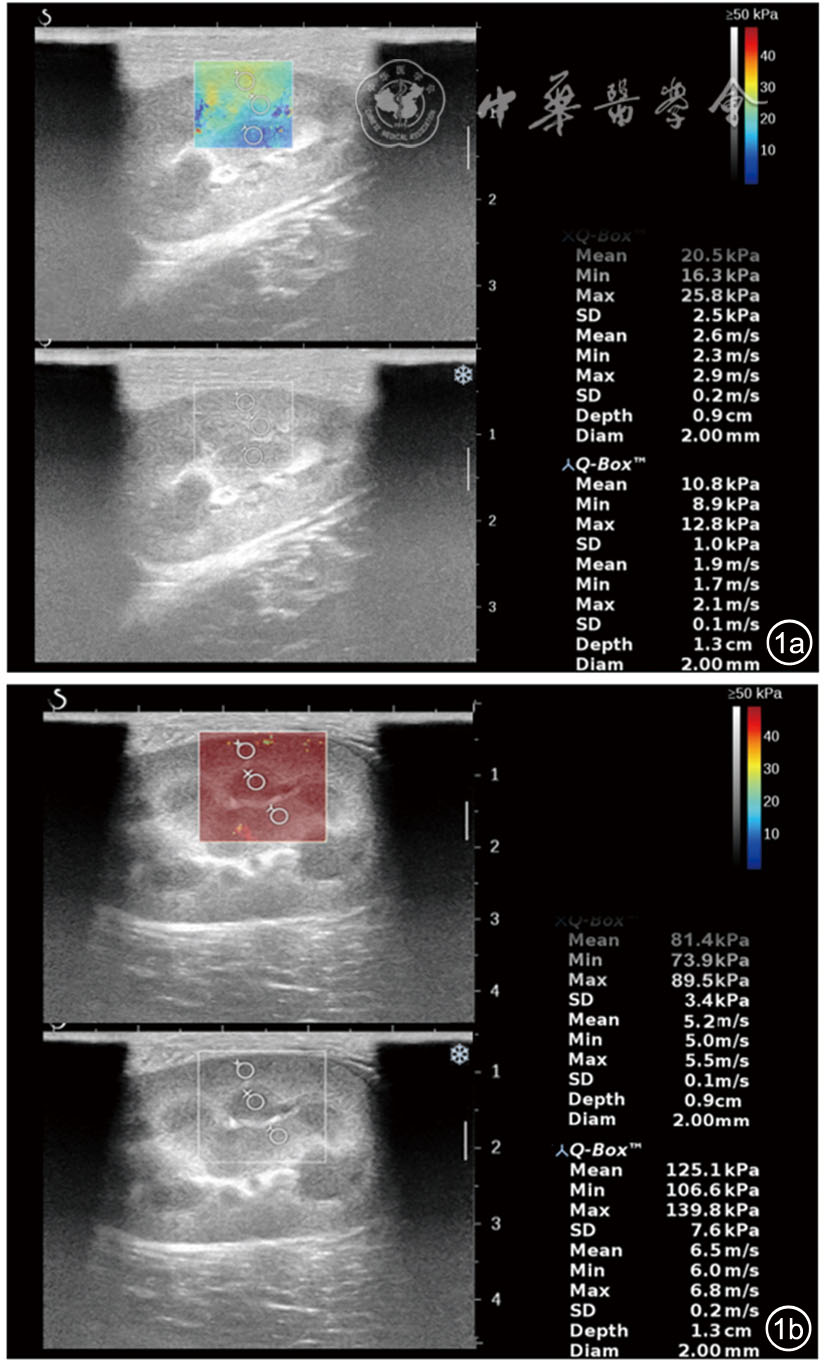

图1 急性肾静脉闭塞健侧与患侧肾脏中部杨氏模量测量图。图a为健侧肾脏中部皮质、髓质及肾窦测量图;图b为患侧肾脏中部皮质、髓质及肾窦测量图